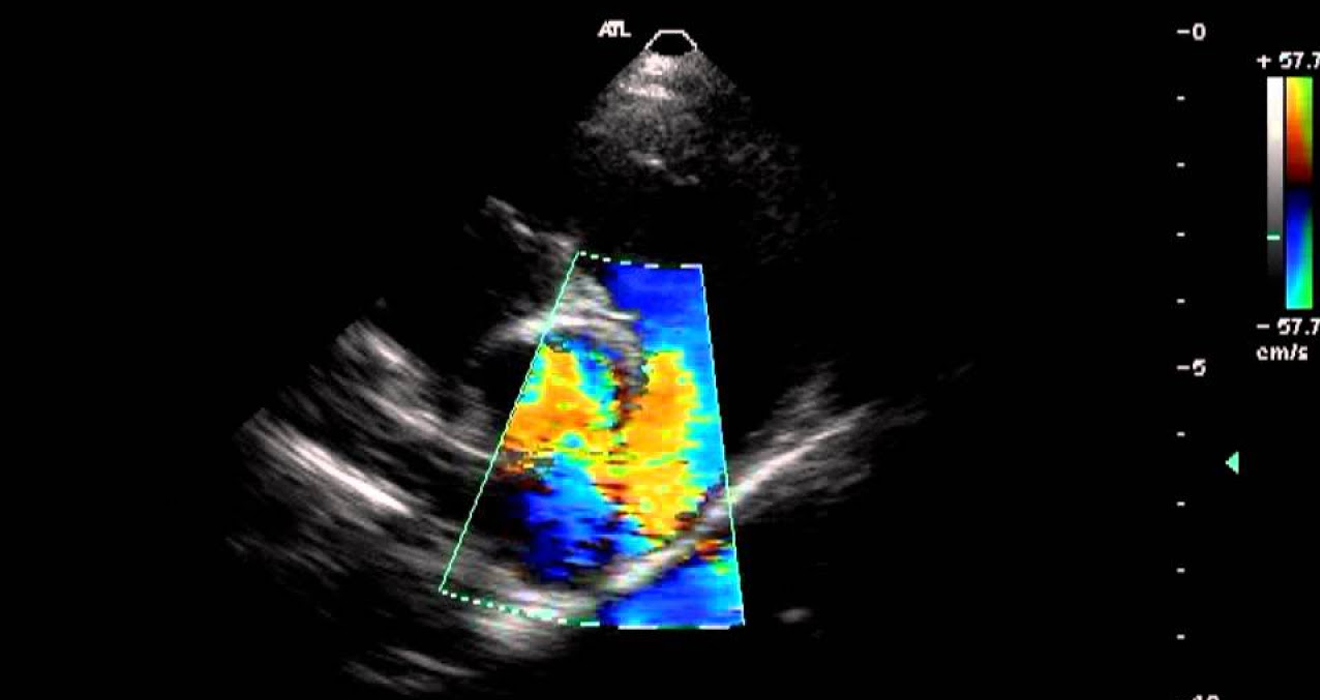

Echo Color Doppler, Echo GLS, and TEE (Transesophageal Echocardiogram)

Echo Color Doppler and Echo GLS (Global Longitudinal Strain) are non-invasive ultrasound tests that provide detailed images of the heart’s chambers, valves, and overall function. These tests are particularly useful in assessing heart function, valve abnormalities, and heart muscle performance.

For more detailed imaging, a Transesophageal Echocardiogram (TEE) is used, where a probe is placed in the esophagus to obtain clearer pictures of the heart’s structure, especially in cases of heart valve disease, clots, or infections.